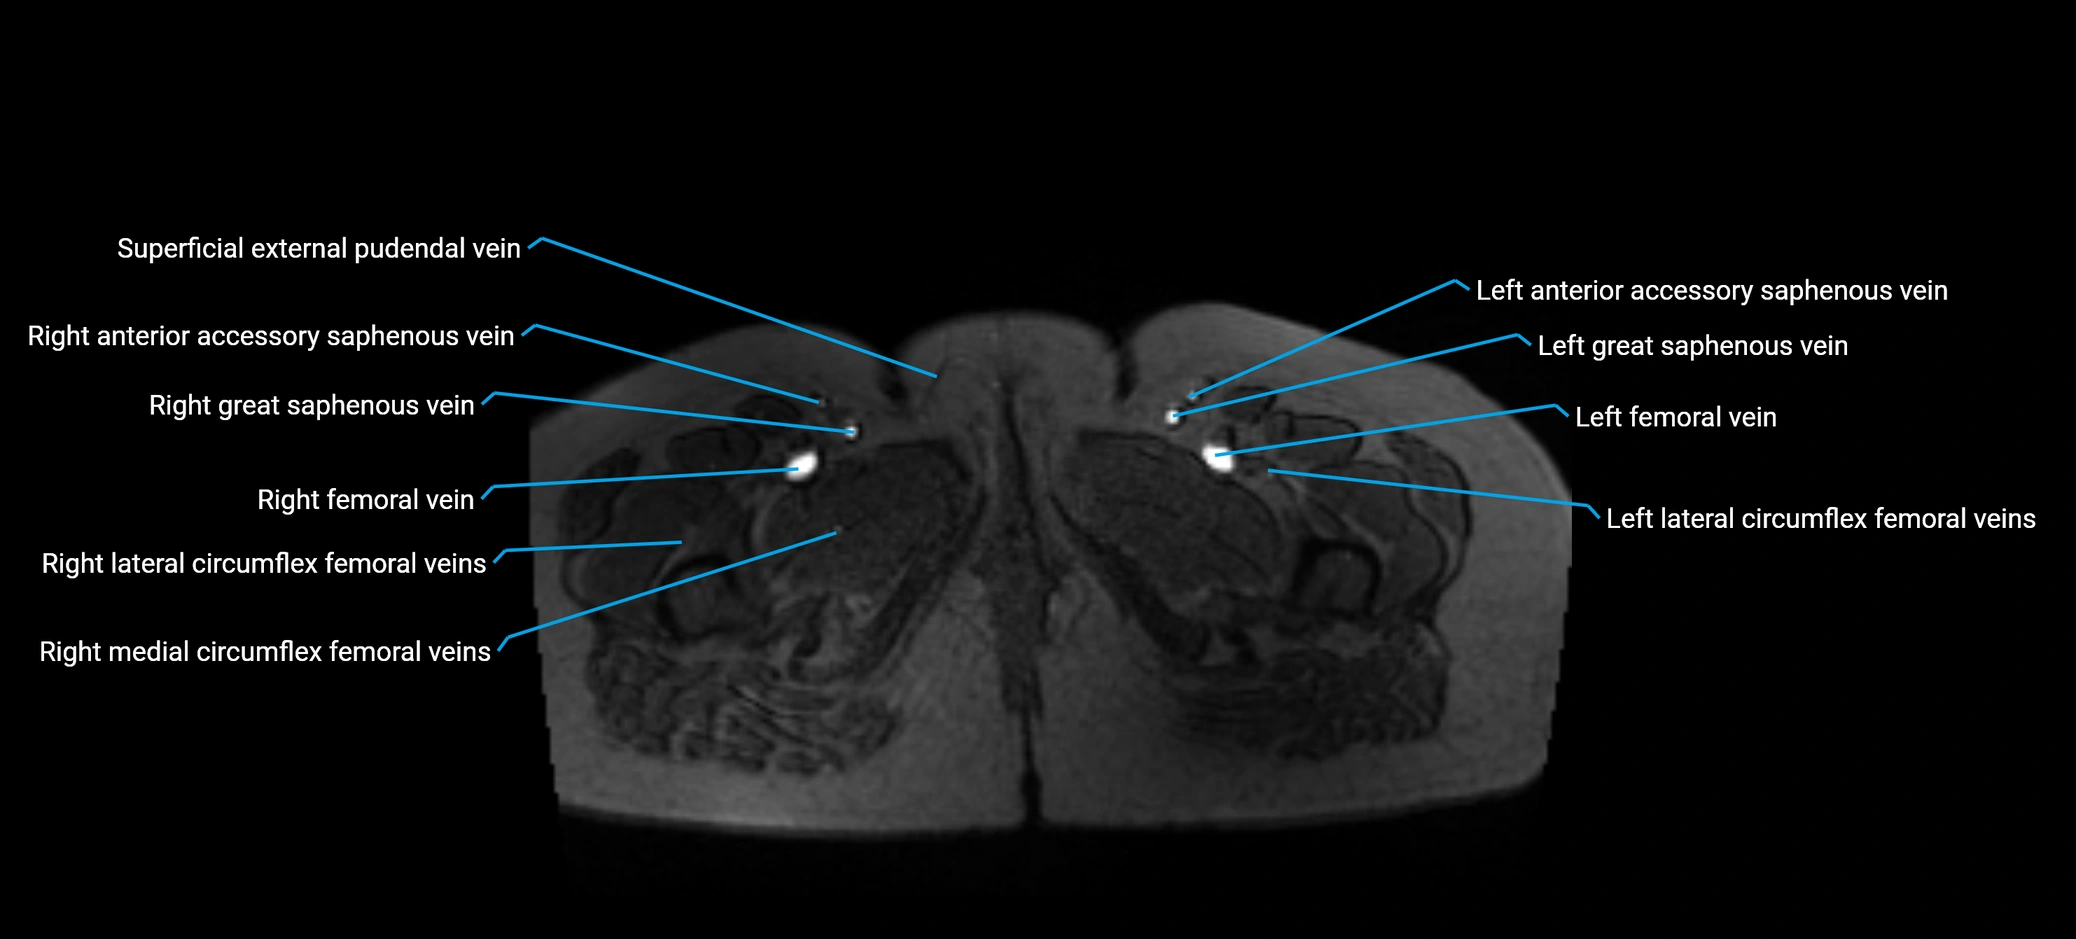

MRI image

image